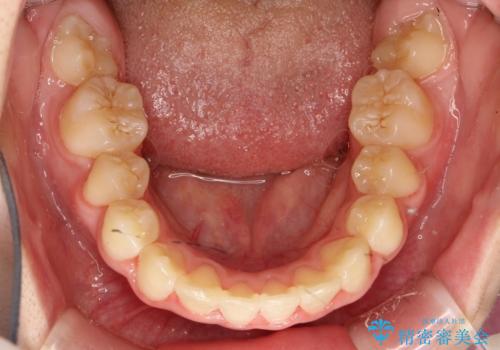

乳歯・過剰歯を除去し、リンガルアーチを用いて埋伏していた犬歯を牽引、その他おおまかな動きを行った後、マルチブラケットにて永久歯の咬合を誘導しました。

一度装置を外し、セトリング含め咬合が安定したら、改めてマウスピース矯正などで微調整を行うとよいかもしれません。